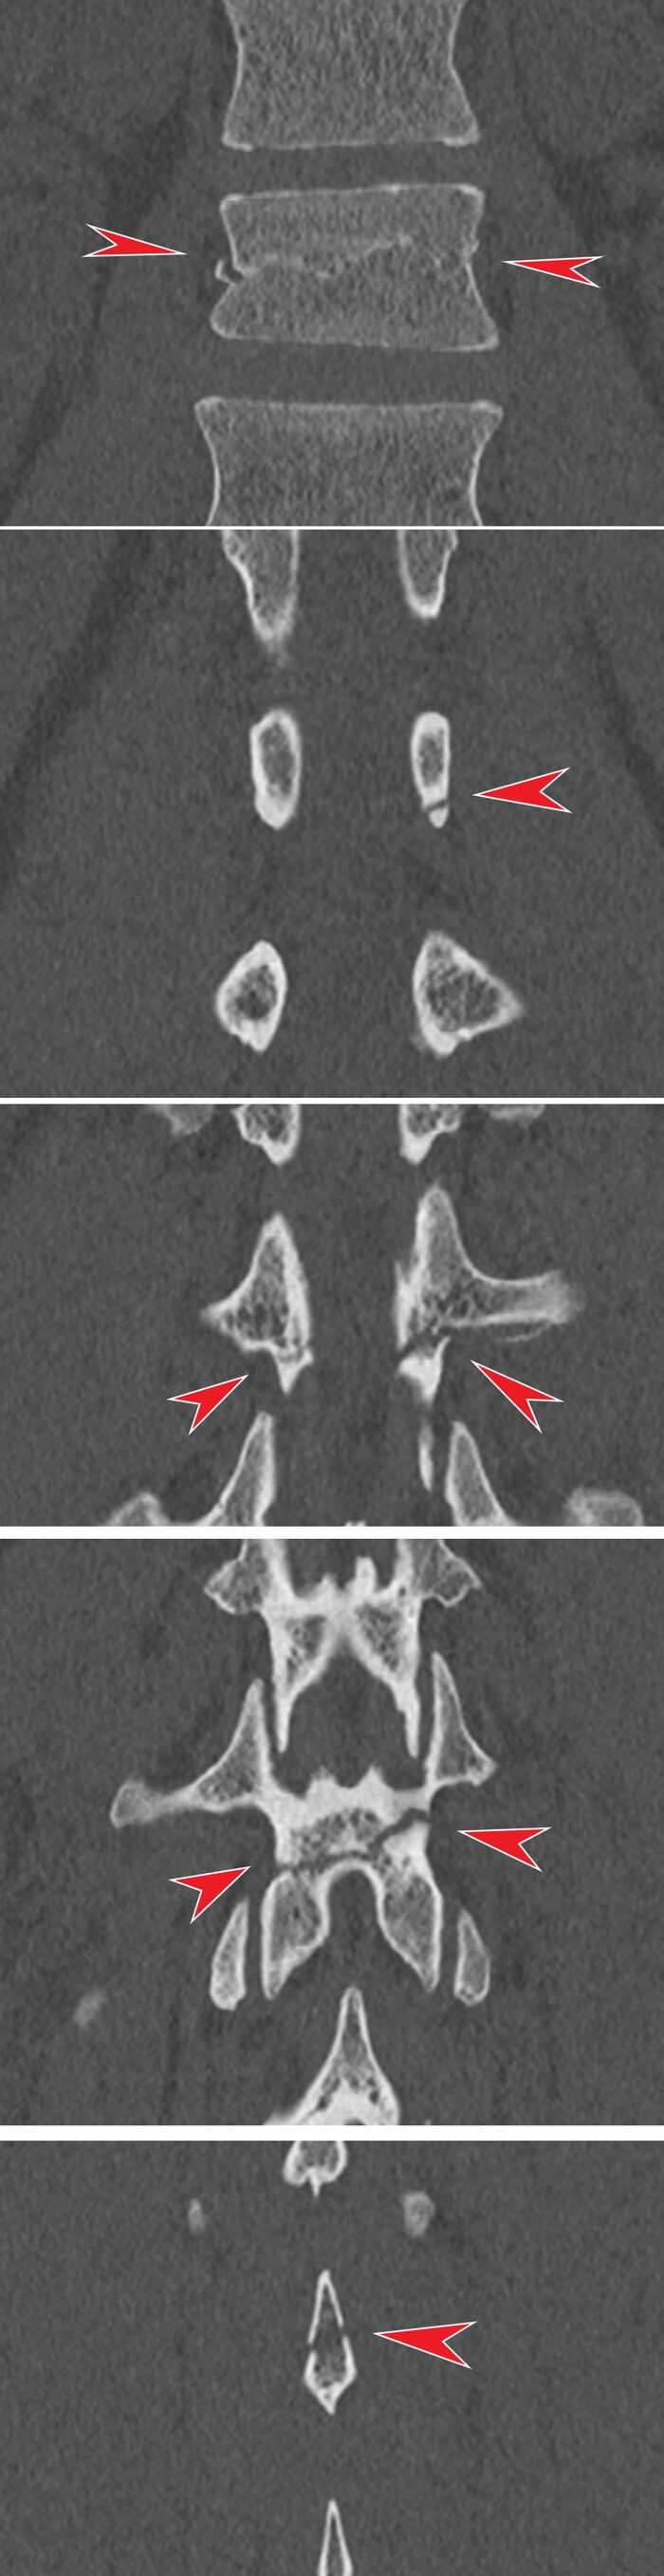

Сделали компьютерную томографию почти всего тела по протоколу множественной травмы (голова, шея, органы грудной клетки + органы брюшной полости включая позвоночник и таз).

Здесь прилагаю только КТ головы, на котором особых патологических изменеий выявлено не было: